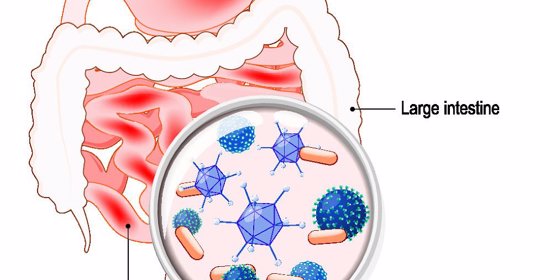

胃食道逆流患者通常可以適量喝優酪乳,但不建議過量飲用。因為優酪乳中含有一定量的乳酸菌和益生元等成分,可以幫助改善腸道微生態環境,促進胃腸蠕動。